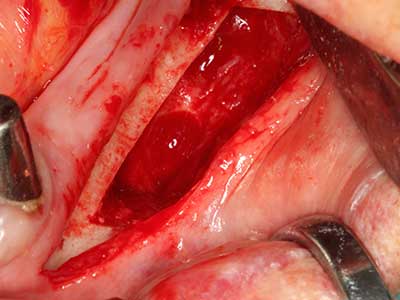

Si es preciso realizar intervenciones quirúrgicas en las que el hueso está en contacto directo con estructuras sensibles, como son los vasos sanguíneos o los nervios, los instrumentos rotativos presentan un enorme potencial de provocar lesiones iatrogénicas. Así, precisamente en la representación de nervios después de una lesión iatrogénica, o en el transcurso de la lateralización de un nervio para resecciones, reconstrucciones o incorporación de implantes, los equipos piezoeléctricos pueden resultar muy útiles para preparar la tapa ósea y retirar las partes de tejido duro cercanas al nervio (fig. 17-20). Por lo general, un ligero contacto del cordón nervioso con el inserto piezoeléctrico no tiene consecuencia alguna; ahora bien, un procedimiento poco cuidadoso con movimientos tipo sierra o piezas de trabajo sobre la base ósea aún existente puede provocar lesiones nerviosas temporales o incluso permanentes. Con todo, el riesgo de sufrir una lesión de este tipo se considera significativamente inferior que en los casos en los que se utilizan sierras y fresas (Pereira, Gealh et al. 2014).

Fig. 18: Preparación de una tapa cortical con la sierra ósea piezoeléctrica (Piezomed, W&H).

Fig. 19: Zona operada después de neurolisis y eliminación del osteomo.

Fig. 20: La tapa ósea extraída se readapta y se fija mediante un tornillo para osteosíntesis (KLS Martin, Tuttlingen).